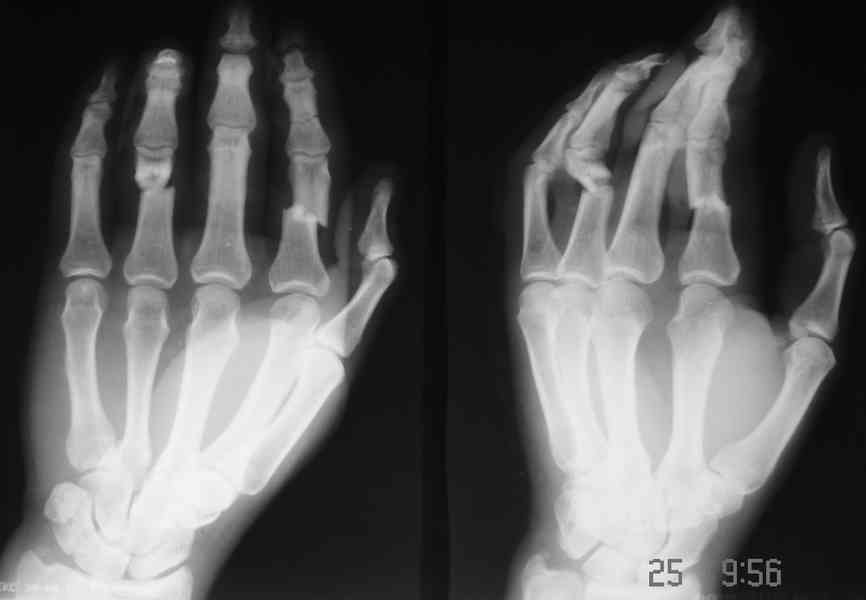

Уважаемые коллеги!Обратился больной с контрактурой 2-4 пальцев кисти. Травма год назад - рука попала в шнек. Планируется оперативное лечение.

При размещении с рисунков "исчезли" подписи, поэтому дополнительно указываю, что первая рентгенограмма - снимок после травмы, вторая - состояие на сегодня. На мой взгляд контрактура прежде всего артрогенная, т.к. ПМФС 2-го и 4-го пальцев находятся в подвывихе. Движения, в существующем на сегодня объеме, свободные - даст-ли тендолиз ожидаемый эффект? Стоит-ли начать с аппарата внешней фиксации? Не приведет-ли одномоментный артролиз и последующая попытка вправления при длительно существовавшем подвывихе к раздавливанию суставными поверхностямя друг друга?

Для того, чтобы понять, действительно ли ПМФС находятся в подвывихе, надо сначала сделать четкую боковую рентгенографю сустава. Особенно это касается второго пальца. Да и на мониторе очень плохо видно состояние головки проксимальной фаланги 4 пальца. И что означает такой интересный объем движений в суставах? Объясните - существует ограничение только активных движений ( и каких?) или еще и пассивных?

Ограничение движений одинаковое и активных и пассивных. Движения в указанном объеме свободные. Чем вызвано ограничение понять пока не можем. В боковой проекции досняли - получается, что подвывиха нет. Вопросов, в отношении того, что мешает стало еще больше.